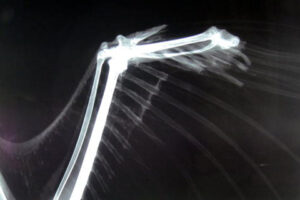

指先の古傷

なんと、このワシは魚の頭ばかりを大量に食べていたことが解りました。検査を進めてゆくと、左翼の指先が骨ごと欠損する古傷を負っていることが明らかになりました。新たに伸びかけた風切り羽も変形し、うまく飛ぶことができず、水産加工場や港で得られる魚のアラを食べながら必死で命を繋いでいたのでしょう。